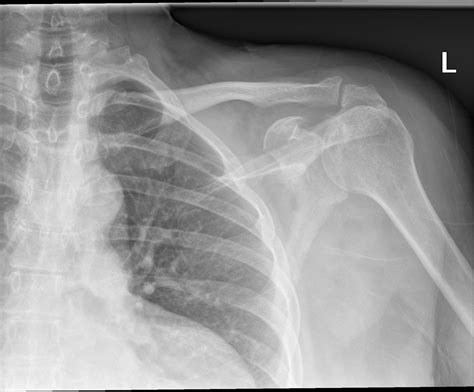

X Ray Shoulder Normal

When you experience persistent shoulder pain or restricted mobility, a medical professional will often order imaging to get a better look at what is happening beneath the surface. One of the first lines of investigation is almost always an X-ray shoulder normal view, which provides a foundational baseline for orthopedic health. Understanding what this diagnostic tool shows and why it is essential for clinical decision-making can help alleviate the anxiety often associated with medical imaging. While an X-ray is a standard procedure, it remains a powerful instrument for identifying fractures, dislocations, and degenerative changes that may be causing your discomfort.

An X-ray of the shoulder is a non-invasive imaging test that uses a small amount of radiation to capture internal pictures of the shoulder bones. This includes the humerus (upper arm bone), the scapula (shoulder blade), and the clavicle (collarbone). By analyzing these images, radiologists and doctors can determine if there are any anatomical abnormalities, structural issues, or signs of disease.

Typically, when a radiologist reports an X-ray shoulder normal result, they are confirming that the skeletal structures are well-aligned, the joint space is intact, and there are no signs of acute trauma or advanced chronic conditions. This is often the starting point for diagnosis; if the bones appear healthy, the physician can then narrow the focus to soft tissue injuries like rotator cuff tears or labral issues, which often require further investigation such as an MRI.

When you undergo this procedure, the imaging team typically captures multiple views to ensure a comprehensive assessment. These usually include an Anteroposterior (AP) view, an axillary view, and a lateral view (often called a "Y-view"). These angles allow the physician to look for specific markers of health:

• Bone Integrity: Ensuring there are no hairline fractures or stress reactions in the humerus or clavicle.

• Joint Space: Checking for smooth, consistent gaps between bones, which indicates healthy cartilage.

• Alignment: Verifying that the humeral head sits correctly within the glenoid fossa (the socket of the shoulder).

• Soft Tissue Shadows: Looking for calcification, which might suggest conditions like calcific tendinitis.